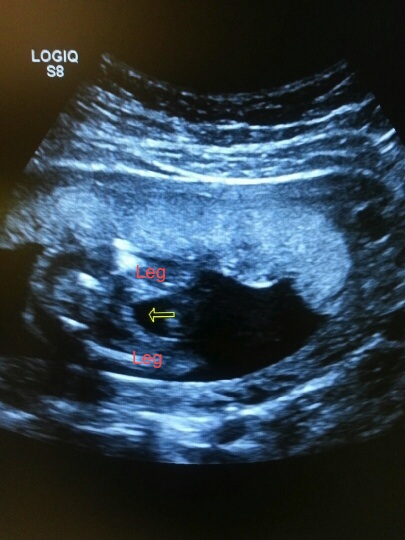

Then, I received another scan by a different office at 21 weeks just to get a second opinion and even I have to agree I didn't see any boy parts, but baby was being a little stubborn. She was sure it was a girl after it was all said and done. Here is the picture we got at that scan:

Attachment 14834